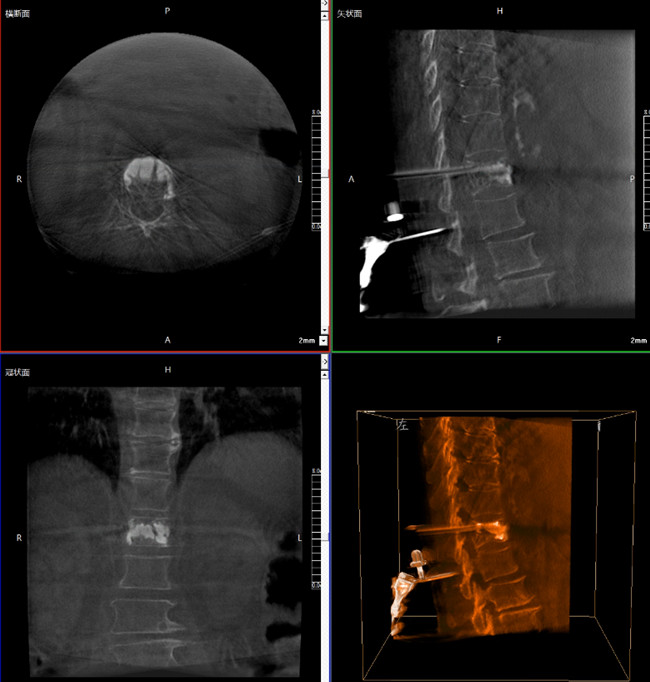

使用普愛醫療三維C形臂對患者進行胸椎影像掃描及三維重建,圖像被同步傳輸到普愛醫療骨科機器人導航系統。

借助骨科機器人的規劃軟件進行術前手術路徑模擬規劃,找到穿刺位置和角度,操作機械臂快速完成手術入點的準確定位。

*骨水泥置入效果良好